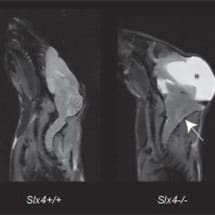

Thirteen genes are known to be inactivated in FA and they all code for proteins that function collectively (the FA repair pathway) in our cells to repair damaged DNA. Scientists are interested in understanding what goes wrong in FA because the inactivated genes play a crucial role in preserving stem cells and enabling normal development of the foetus. To date how the FA repair pathway functions and why it should be so crucial for stem cell function, foetal development and cancer suppression has been elusive. KJ’s group have discovered a new gene in the mouse FA pathway known as SLX4. SLX4 is the first gene identified in the FA pathway which is clearly involved in DNA repair and links with enzymes that cut DNA. When this gene is inactivated in mice, the mutant animals display most of the features seen in the human FA illness and these mice therefore provide for the first time a disease model for this human condition. Two other papers are also published in the same volume of Nature Genetics which demonstrate that inactivation of SLX4 causes FA in humans.

This study was made possible by collaboration between Dr David Adams at the Wellcome Trust Sanger Institute (where the knockout animal was generated by the EUCOMM consortium) and Professor Kevin Brindle and his team at the CRUK CRI (who carried out state-of-the-art image analysis of mutant animals).